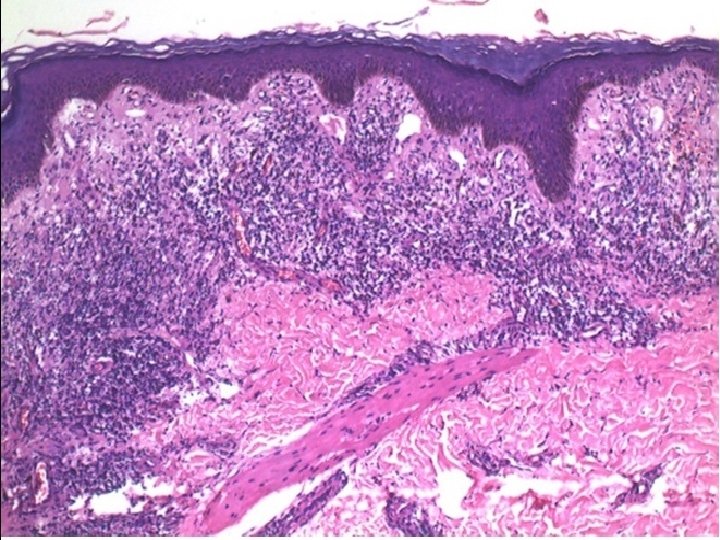

� Skin biopsy from a plaque on the chest showed a moderately dense superficial and deep perivascular and periappendageal infiltrate of lymphocytes, histiocytes and plasma cells. The infiltrate in the upper dermis was present close to the epidermis in a patchy lichenoid pattern. The epidermis showed mild hyperplasia, spongiosis with neutrophils and focal parakeratosis.